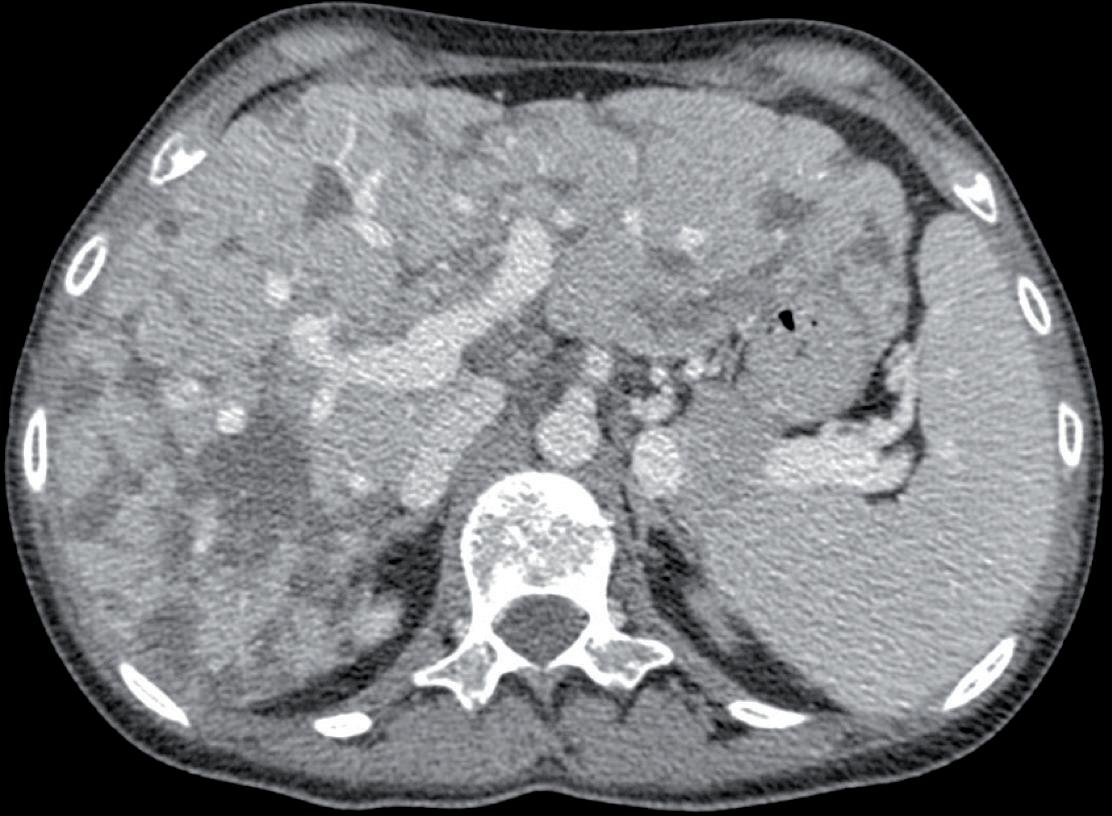

Dopo soli 4 mesi, alla prima rivalutazione con TC Totalbody, si evidenziava una progressione epatica di malattia. Alla luce della rapida progressione si decideva di effettuare una nuova ricaratterizzazione di malattia tramite biopsia di lesione epatica. L’esame istologico deponeva per carcinoma duttale infiltrante ER 95%, PgR 15%, Ki-67 45%, HER2 positivo (IHC 3+).

Si candidava pertanto la paziente ad una prima linea di trattamento standard per malattia metastatica HER2 positiva, ovvero con pertuzumab (420 mg) + trastuzumab (6 mg/ kg) q21 + paclitaxel (80 mg/mq) q7 1. Dopo circa 6 mesi di trattamento secondo tale schema, in considerazione del buon controllo di malattia ottenuto (risposta parziale di malattia a livello epatico), veniva sospeso il trattamento chemioterapico, proseguendo una terapia di mantenimento con pertuzumab + trastuzumab in associazione ad inibitore dell’aromatasi. A Dicembre 2021, dopo soli 3 mesi di terapia di mantenimento, si evidenziava una progressione epatica ed ossea alla TC Total-body di rivalutazione. Si candidava pertanto la paziente ad una ulteriore linea di trattamento con il farmaco TDM-1 (3,6 mg/kg q21), che, al momento di tale decisione terapeutica, rappresentava la terapia standard di seconda linea nel carcinoma mammario metastatico HER2 positivo 4. A Marzo 2022, dopo soli 3 mesi di trattamento, la TC total-body di rivalutazione evidenziava una progressione dimensionale e numerica delle lesioni a livello epatico, incremento dimensionale della lesione sternale e dei linfonodi della catena mammaria interna sinistra. Siamo ad inizio 2022, ed il nostro studio di riferimento in questo setting è il DESTINYBreast015. La paziente veniva pertanto avviata a trattamento con trastuzumab deruxtecan 5,4 mg/kg endovena q21. Tuttavia, dopo 2 cicli di terapia con T-DXd, la paziente veniva ricoverata per iniziale scompenso cardiaco (comparsa di edemi declivi e lieve dispnea). All’ecocardiogramma di controllo si evidenziava una

normale attività contrattile cardiaca, sovrapponibile ai precedenti controlli, ma si riscontrava un quadro di insufficienza mitralica. Veniva dunque impostata terapia diuretica (furosemide) e la paziente veniva dimessa. Veniva contestualmente richiesta una rivalutazione strumentale di malattia che mostrava una importante risposta di malattia a livello epatico (figura 1), linfondale e della lesione sternale. Alla luce della rapida risposta al trattamento con T-DXd, discusso il caso con gli specialisti di cardioncologia che hanno considerato l’episodio di scompenso cardiaco come non imputabile alla terapia anti-HER2, si è deciso di riprendere il trattamento con T-DXd, impostando un follow-up cardiologico con ecocardiogramma ogni 3 mesi e dosaggio di pro-BNP e troponina ogni 3 mesi, aggiungendo inoltre bisoprololo alla terapia domiciliare della paziente con finalità cardioprotettiva. La paziente proseguiva quindi T-DXd sempre alla dose di 5,4 mg/kg, con mantenimento di una normale funzionalità cardiaca, in assenza di alterazione nei valori laboratoristici di troponina e pro-BNP. Le uniche tossicità riportate sono state astenia G1 e anemia G1. Purtroppo, la TC di Settembre 2023 ha mostrato una progressione di malattia, sia a livello epatico che a livello osseo. La paziente è stata successiva trattata con la combinazione di capecitibina (1000 mg/mq BID consecutivamente per 14 giorni q21) + tucatinib (300 mg 2 volte al giorno continuativamente) + trastuzu -